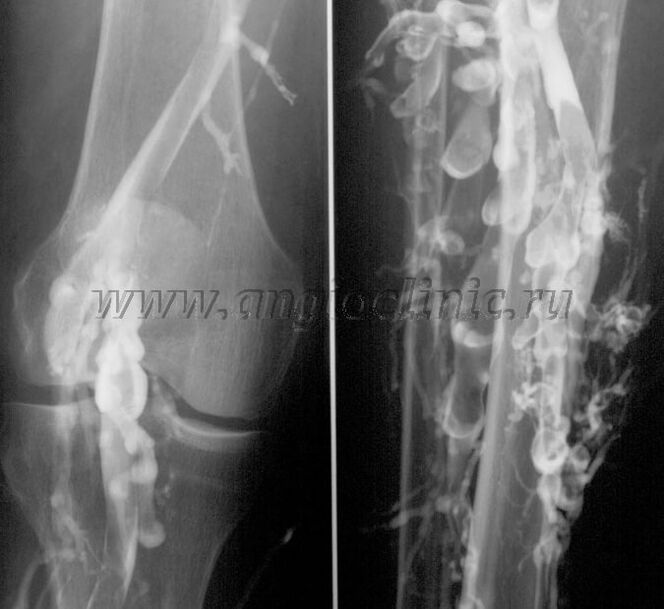

Kontrastná venografia

Zvyčajne na úplnú diagnostiku venóznej patológie postačuje ultrazvukové vyšetrenie, ale v niektorých prípadoch je potrebné študovať vzťah medzi stavom hlbokého a povrchového žilového systému, najmä v prípade relapsov kŕčových žíl a sekundárnych kŕčových žíl.

Na vyriešenie týchto problémov sa používa kontrastné röntgenové vyšetrenie. Safény sa prepichnú a podá sa kontrast. Pohyb kontrastu sa pozoruje na monitore röntgenového prístroja a vykonajú sa všetky potrebné testy a projekcie. V súčasnosti sa venografia na kŕčové žily používa veľmi zriedkavo.